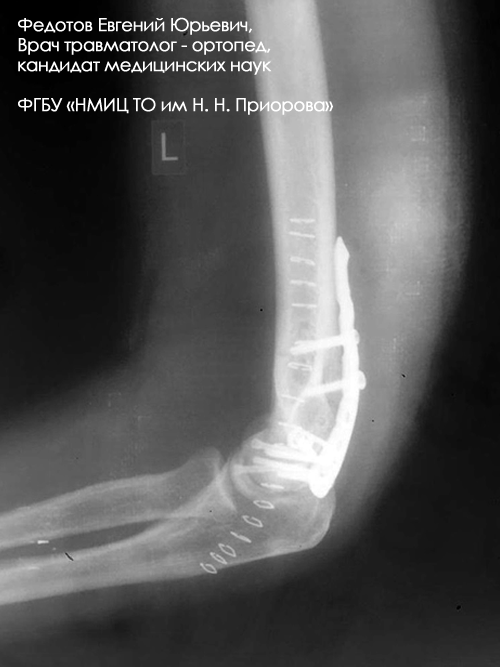

Пациентка с чрезвычайно тяжелым повреждением: тяжелым внутрисуставным переломом нижнего отдела плечевой кости с повреждением локтевого сустава с перелом средней трети локтевой кости со смещением отломков (дорожная травма).

Рентгенограмма до операции.

Выполнена операция: металлоостеосинтез плечевой кости пластинами LCP, анатомия локтевого сустава полностью восстановлена, остеосинтез локтевой кости стержнем с блокированием через небольшие разрезы-проколы (до 1 см.).

Гипсовая повязка после операции не применялась, сразу разрешена разработка движений в суставах конечности. Результат через 3 недели после операции. Уже видна хорошая функция конечности.

Результат через 4 мес. после операции. Функция конечности полностью восстановлена. Конечность ничем не отличается от здоровой.